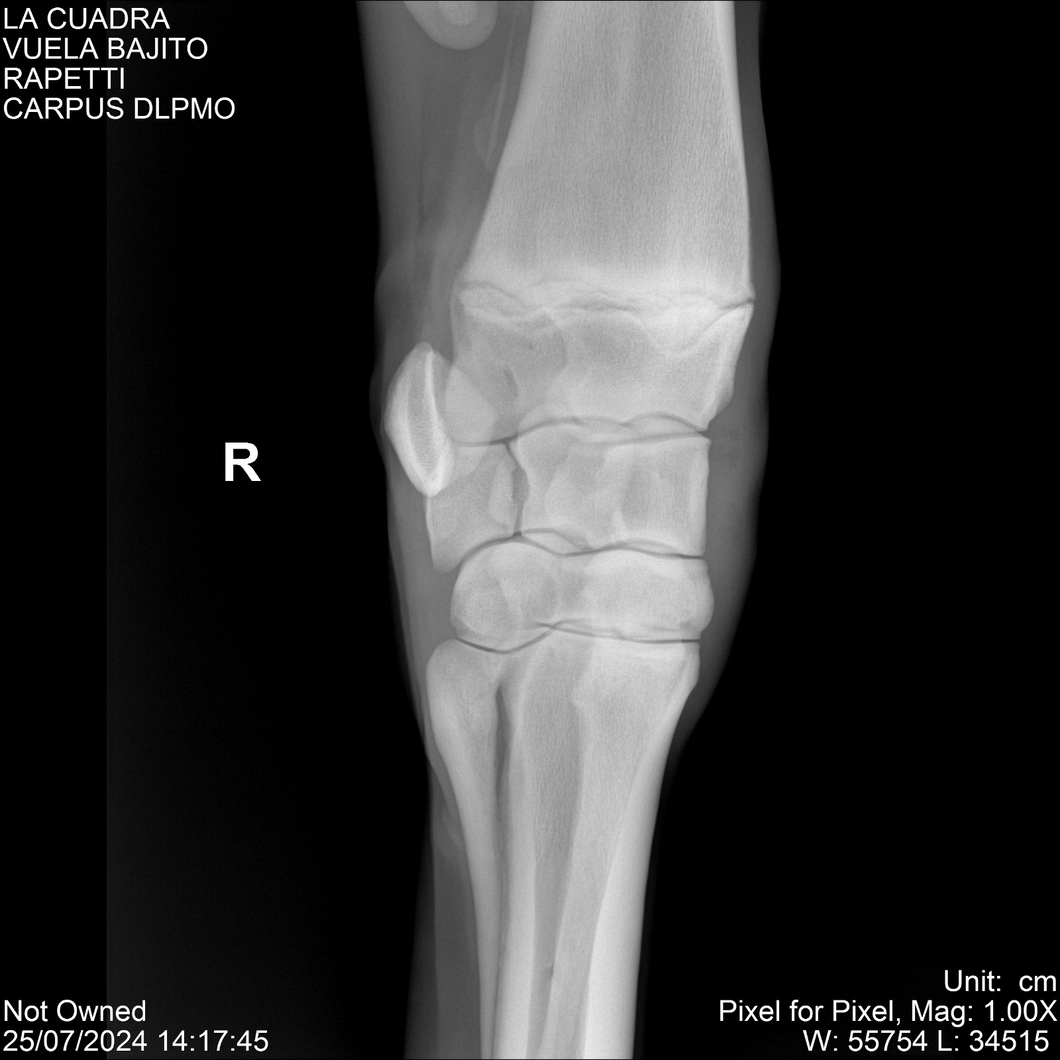

LOTE 16, VUELA BAJITO Lote Anterior Volver al remate Lote Siguiente Ficha Contacto Montevideo - Ficha del Lote Identificador: #284451 Categoría: Yeguarizos Montevideo - 77 Visualizaciones ClicData Contacto Empresa: Abelenda N. R., Walter Hugo Nombre*: Teléfono* : E-mail* : Mensaje Enviar Registrese gratis Este contenido Exclusivo está disponible sólo para usuarios registrados Ingresar